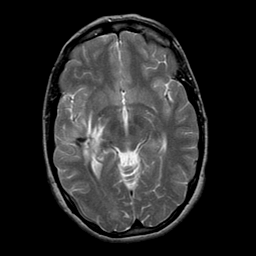

overlay -- Slice #12

[Home][Help][Clinical] Slice 12